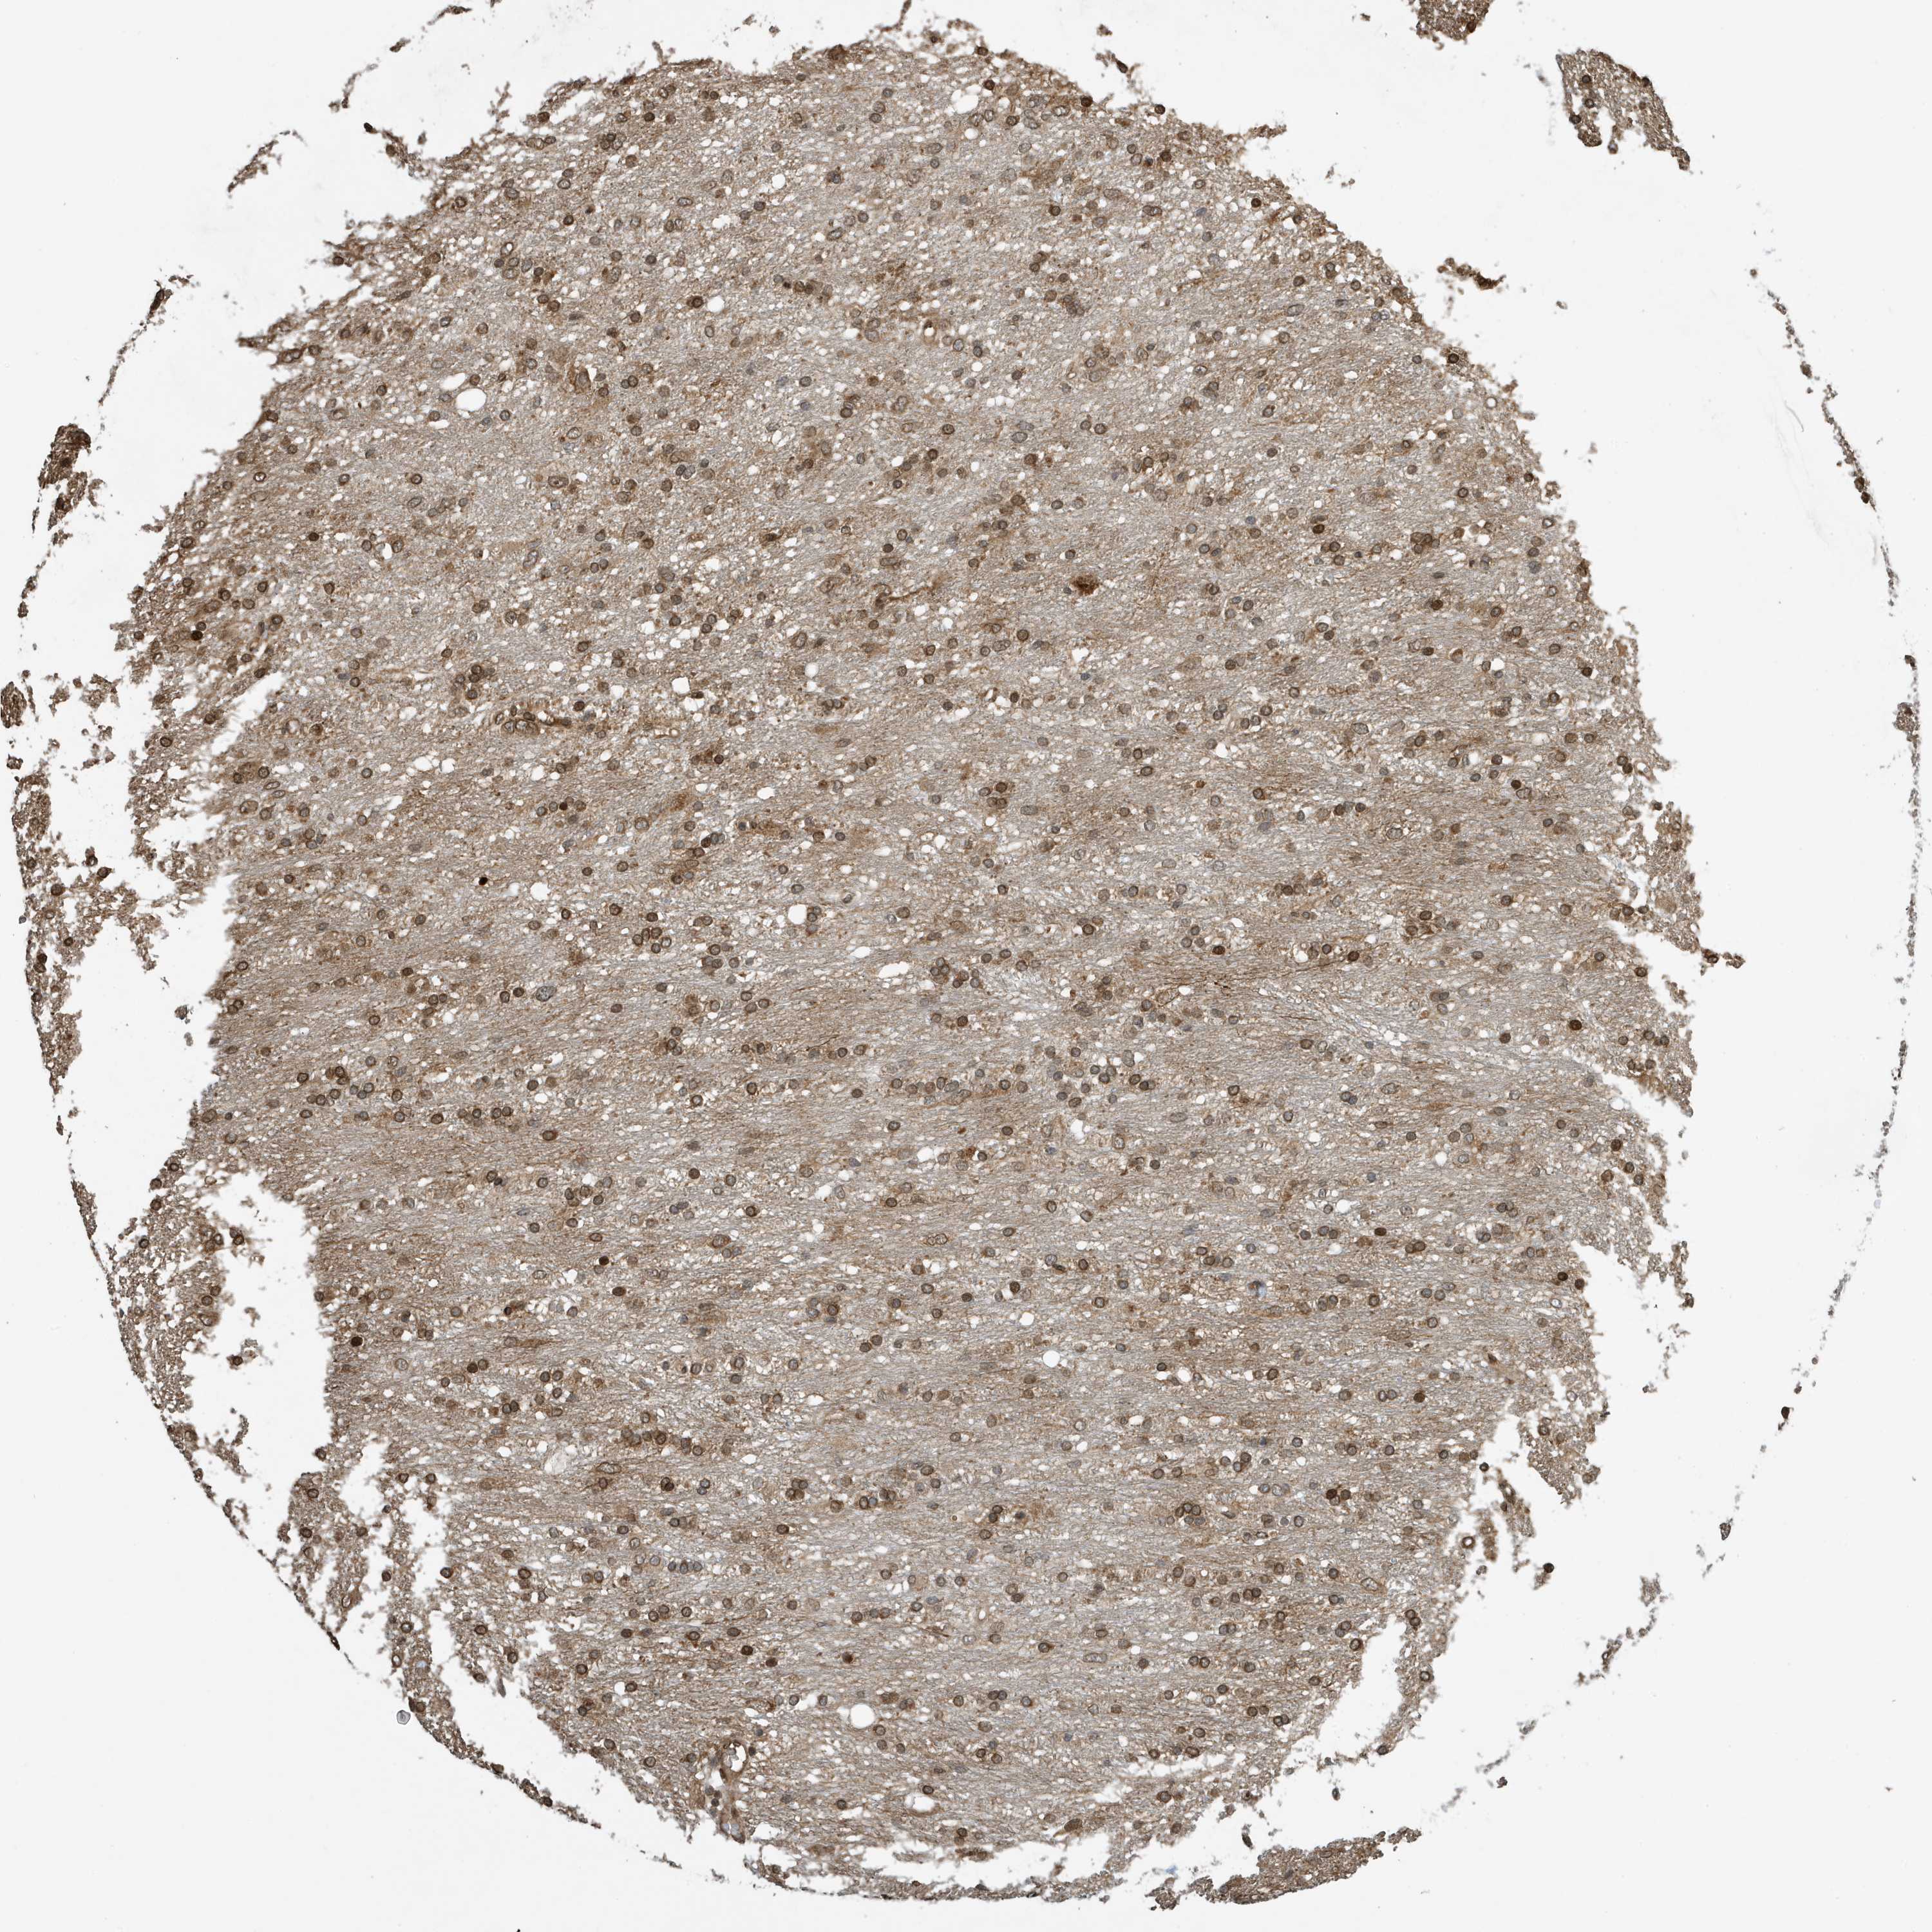

GLIOMA - Protein expressioni

A mouse-over function shows sample information and annotation data. Click on an image to view it in a full screen mode. Samples can be filtered based on level of antibody staining by selecting one or several of the following categories: high, medium, low and not detected. The assay and annotation is described here.

Note that samples used for immunohistochemistry by the Human Protein Atlas do not correspond to samples in the TCGA dataset.

Antibody stainingi

Antibody staining in the annotated cell types in the current human tissue is reported as not detected, low, medium, or high, based on conventional immunohistochemistry profiling in selected tissues. This score is based on the combination of the staining intensity and fraction of stained cells.

Each image is clickable and will lead to virtual microscopy that enables deeper exploration of all samples and also displays staining intensity scores, fraction scores and subcellular localization as well as patient and tissue information for each sample.

Antibody CAB034070

Staining

High

Medium

Low

Not detected

Intensity

Strong

Moderate

Weak

Negative

Quantity

>75%

75%-25%

<25%

None

Location

Nuclear

Cytoplasmic/membranous

Cytoplasmic/membranous,nuclear

Glioma, malignant, High grade

Glioma, malignant, Low grade